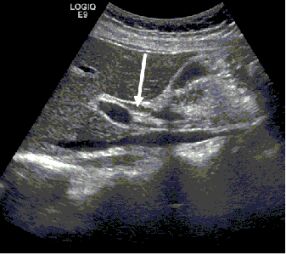

70.附圖為右上腹部超音波斜縱向掃描,箭號所指的構造最可能為下列何者? (A)膽囊(gallbladder)(B)總膽管(common bile duct)(C)下腔靜脈(inferior vena cava)(D)門靜脈(portal vein)